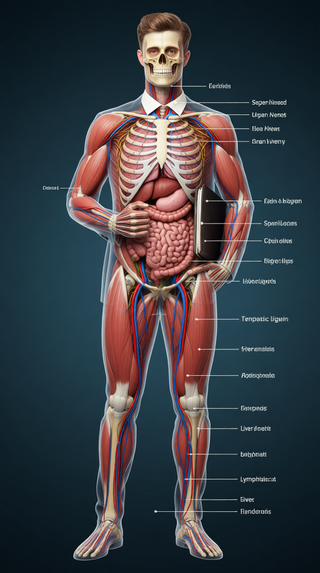

Creates ultra-detailed, multi-layer 3D anatomical visualizations from reference photos.Open

Creates ultra-detailed, multi-layer 3D anatomical visualizations from reference photos.Open

Transform photos into scientific anatomical illustrations.Open

Transform photos into scientific anatomical illustrations.Open